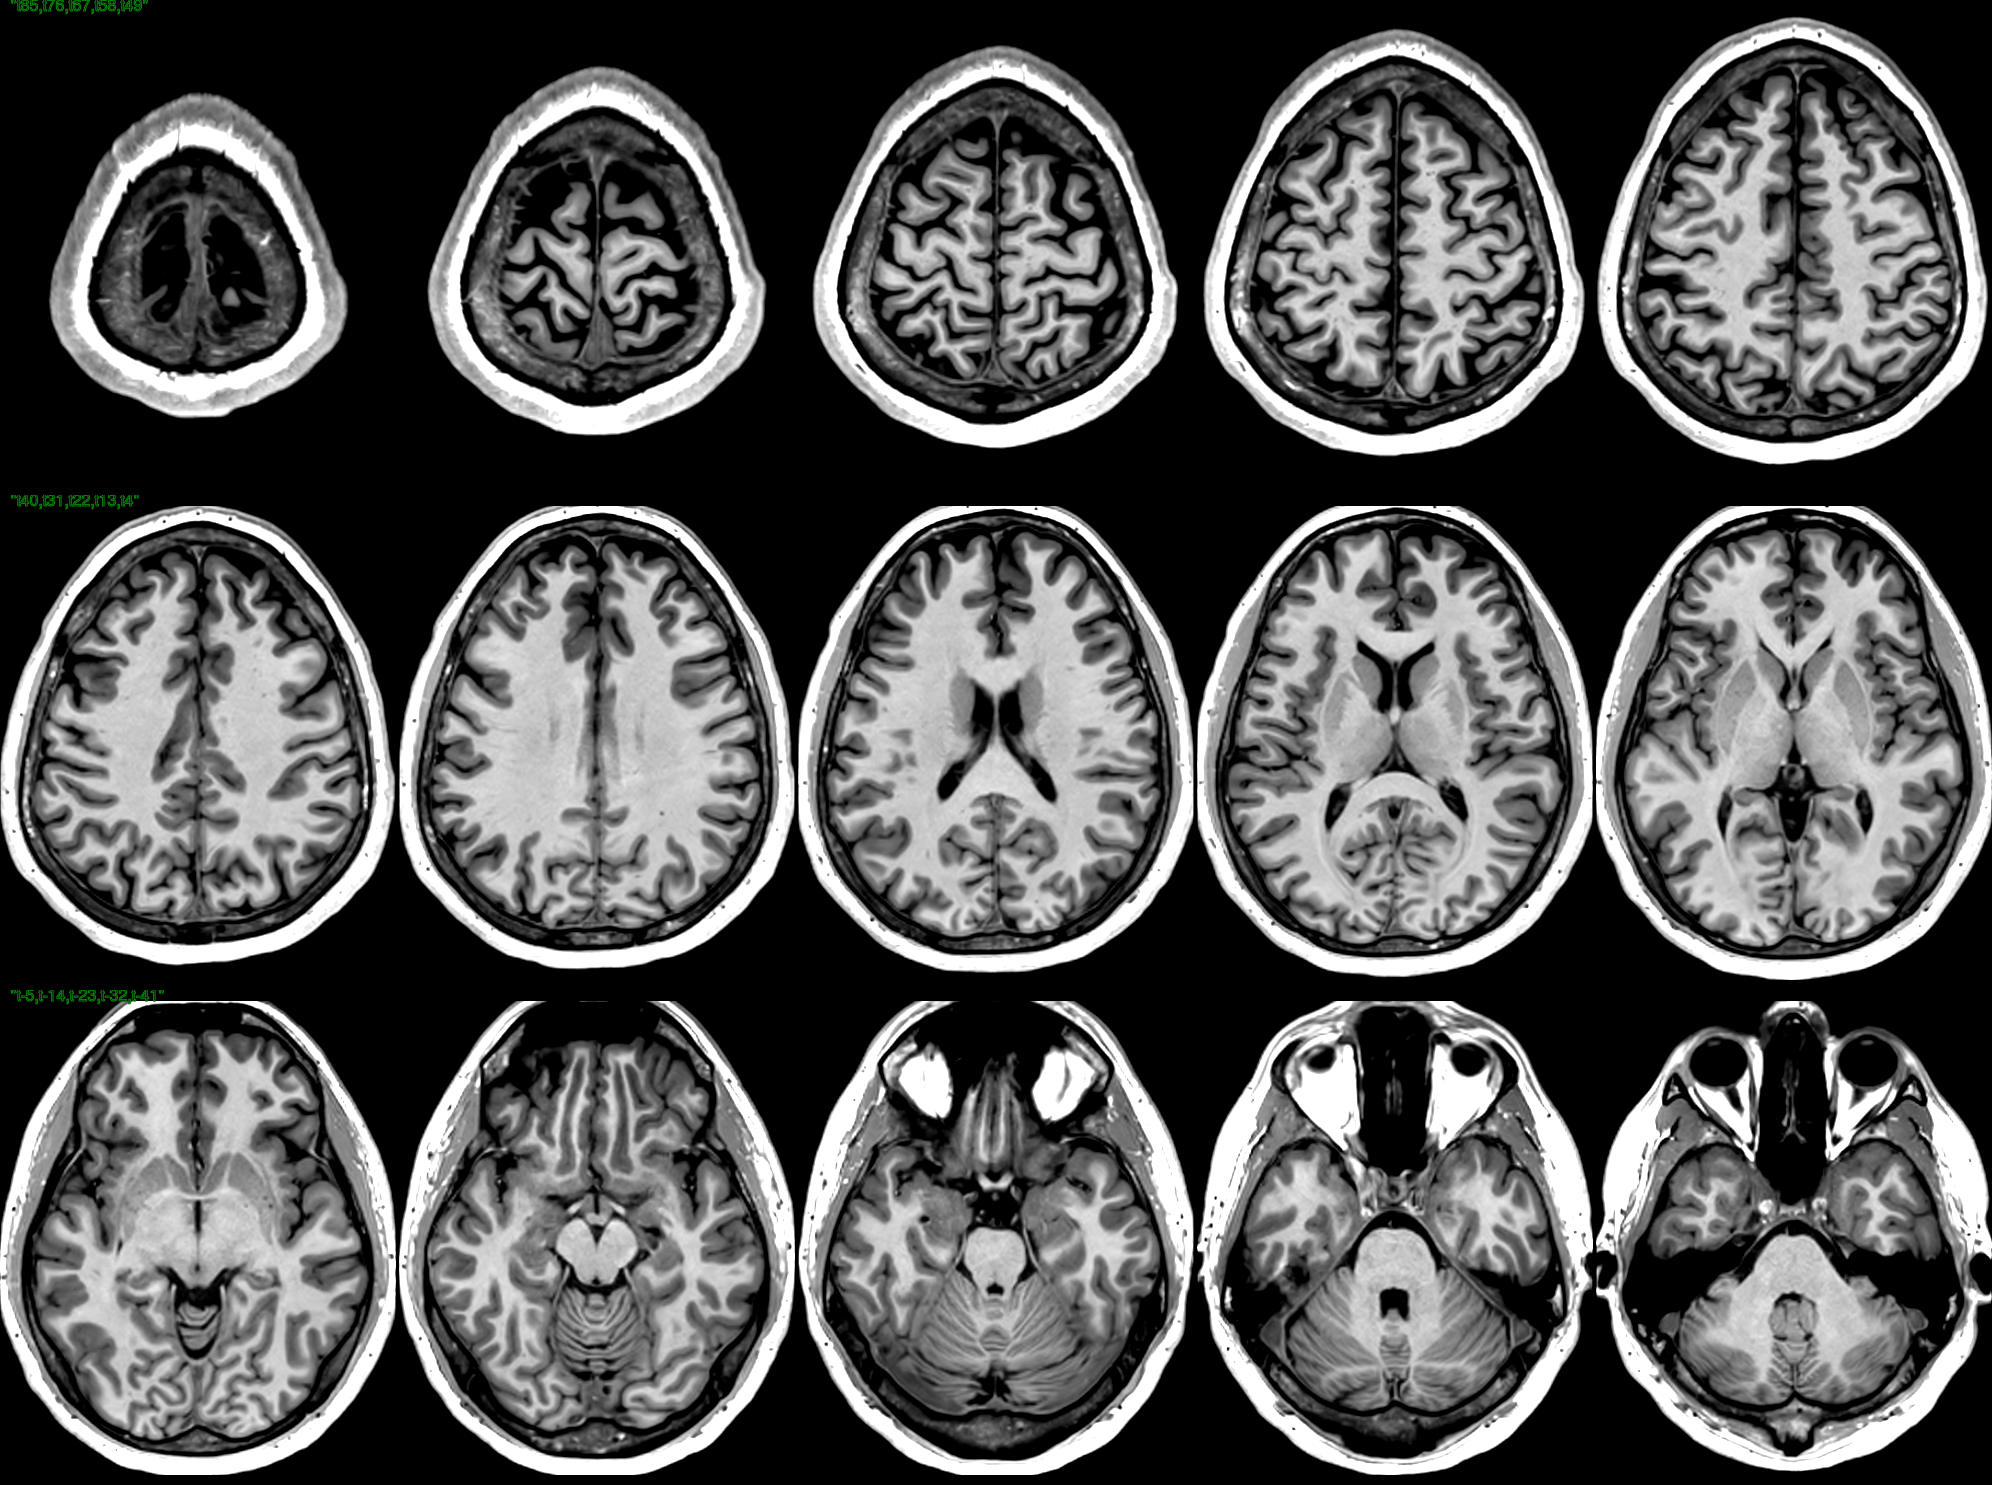

T1 Images